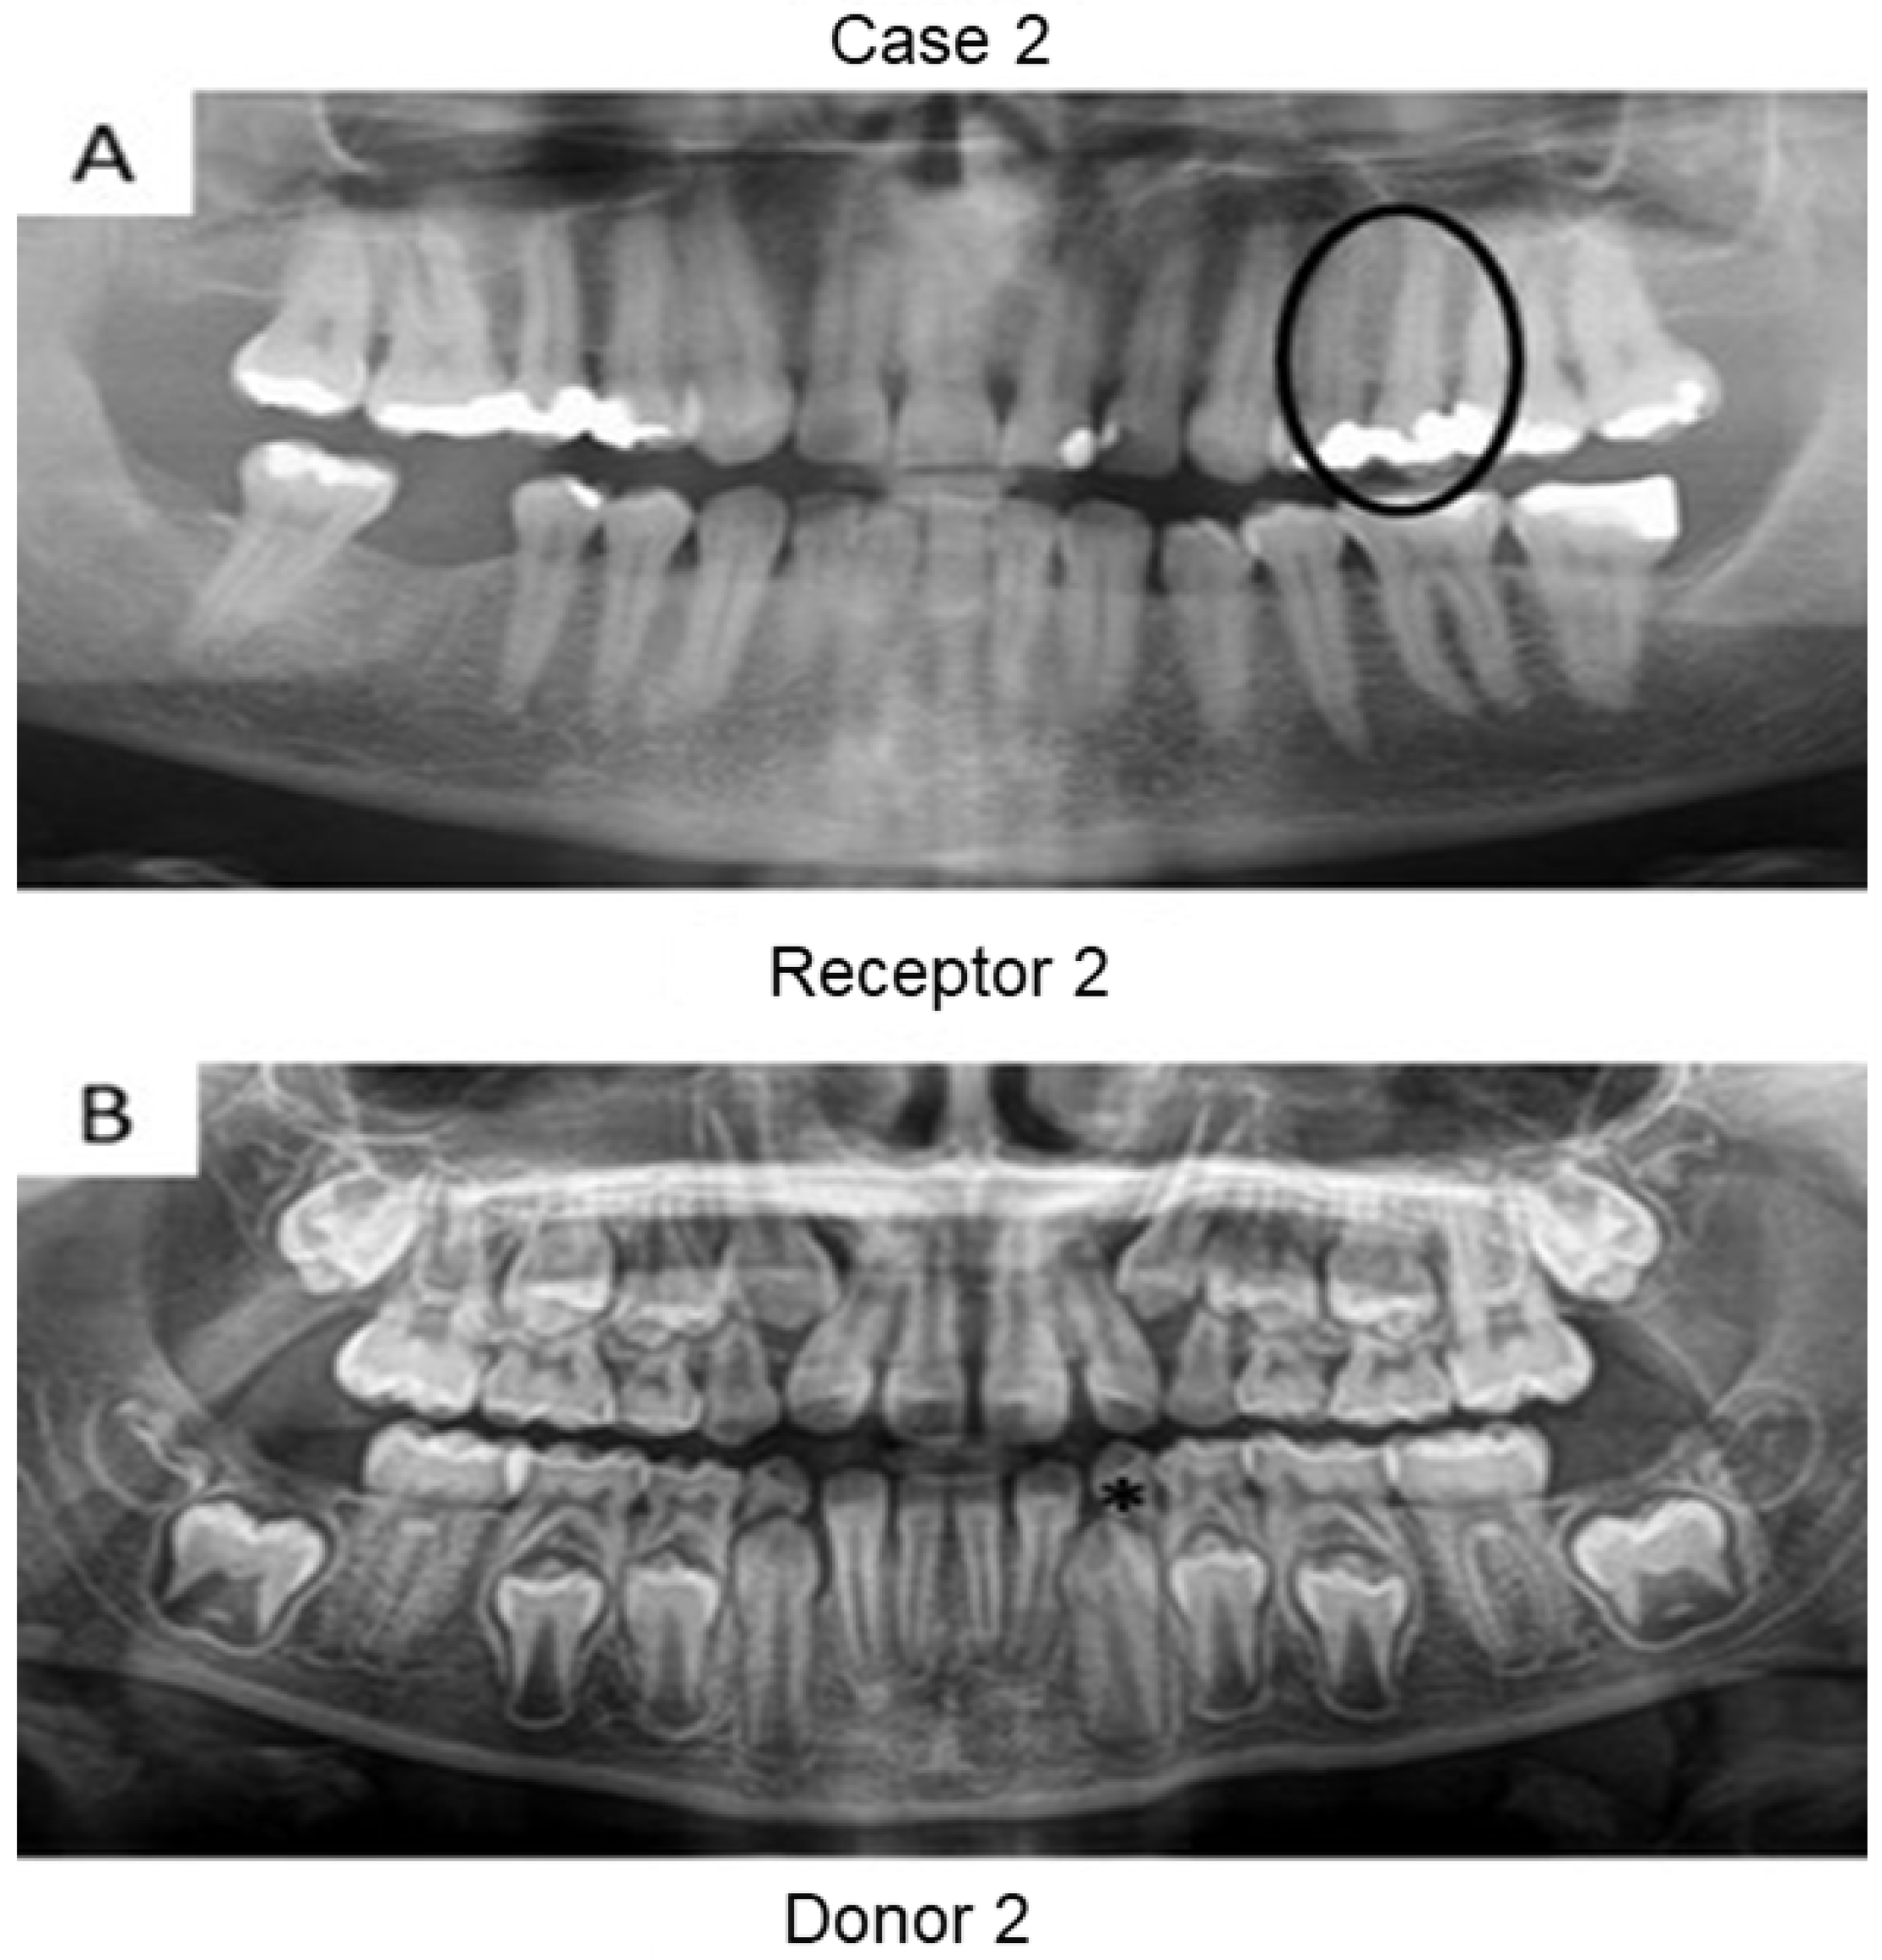

First, panoramic radiography was performed on all patients in the three cases (Figure 1, Figure 2 and Figure 3), as well as computed tomography (CT) scanning with a 0.25 mm voxel size in order to confirm the periapical status of each tooth requiring endodontic treatment. The extraction of teeth from the patients’ children was performed without tooth sectioning and with extreme caution in order to avoid damaging the tooth and the apical structures. The extraction was carried out with local anesthesia using 1.8 mL of 2% lidocaine (1:80,000 epinephrine) through a nerve block technique. The extracted teeth were stored in a sterilized saline solution. At the same time and in the same dental office, the single-root teeth requiring root canal treatment were also anesthetized as aforementioned, isolated with a rubber dam, and pulp chamber access was executed with diamond burs with a high-speed handpiece under continuous and copious water irrigation. The canal instrumentation was performed using rotary files (Wave One Gold, Dentsply, Rio de Janeiro, Brazil) in combination with irrigation using a tri-antibiotic solution (ciprofloxacin, minocycline, and metronidazole at 500 μg/mL each) [14,15]. Prior to the rotary files, one #10 manual K-file (Dentsply) was used to perform the patency. No apical bleeding was performed because it was a different protocol than the revascularization strategy [15,16].

Figure 2. Panoramic radiographs of initial visit of the two patients in case 2. Black circle indicates the tooth requiring root canal treatment (receptor tooth) in the father whilst the asterisk points to the primary canine of the patient’s daughter planned for extraction (pulp donator tooth).